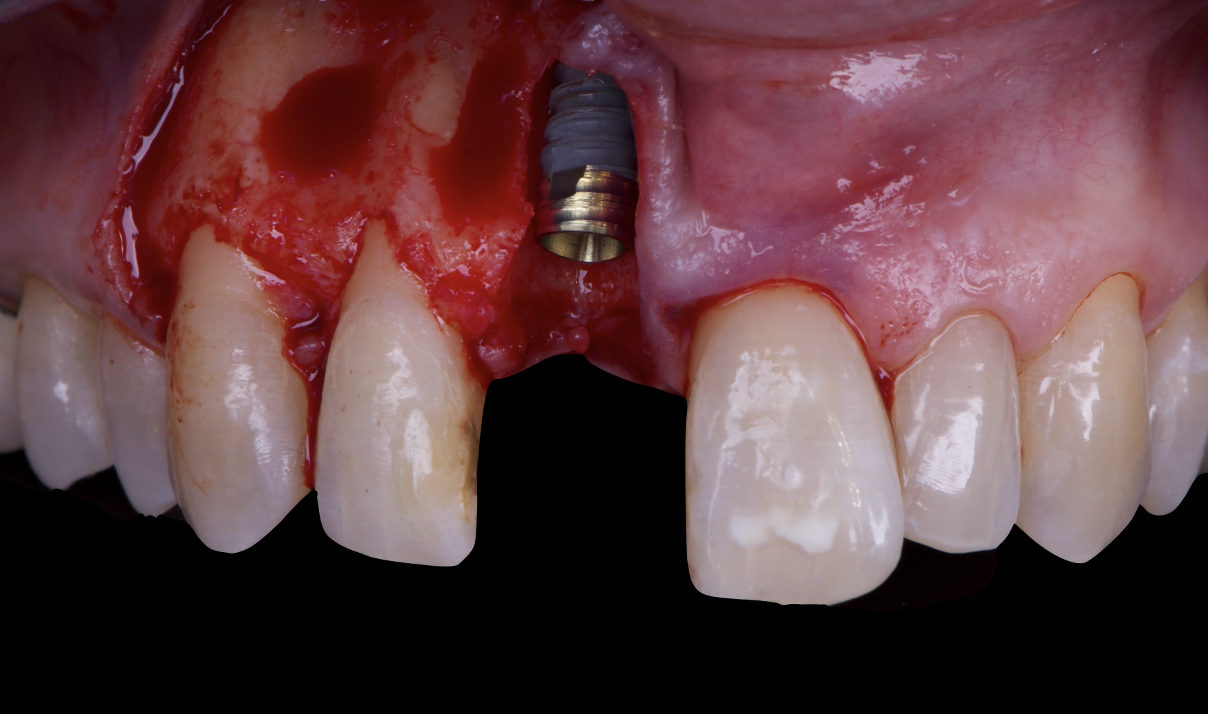

The surgical protocol began with the atraumatic extraction of tooth 1.1 to preserve as much of the alveolar socket as possible. Immediately following extraction, an N1 implant was placed into the socket using a guided surgical approach to ensure ideal three-dimensional positioning. The “one abutment one time” technique was applied to minimize soft tissue manipulation during the healing phase, which is particularly important in esthetic areas.

Given the significant buccal defect, guided bone regeneration (GBR) was performed simultaneously. A mixture of autologous bone and creos™ xenogain™ was applied to the defect and covered with a resorbable creos™ membrane to restore ridge width and support the buccal contour. In addition, a connective tissue graft was harvested and placed in the vestibular region to increase the thickness of keratinized mucosa. This combined approach addressed both hard and soft tissue deficiencies, providing the biological foundation for a stable and esthetic outcome.

On the same day as the surgery, an immediate-load provisional crown was delivered. This restoration was fabricated in acrylic resin and screw-retained on the implant, following the “one abutment one time” principle. The provisional crown was carefully adjusted to avoid occlusal loading while supporting the peri-implant soft tissue architecture during the healing phase.